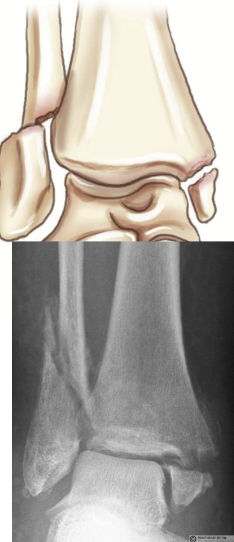

What type of fracture is this?

Pott

What is a pott fracture?

Complete fracture of distal fibula, may involve ligament damage and fracture of medial malleolus and distal tibia